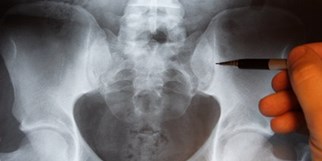

Arthroskopisches Operieren ist auch als so genannte Schlüsselloch-Chirurgie bekannt. Bei Operationen am Ellbogen-, Knie-, Schulter- und Sprunggelenk gilt dieser minimalinvasive Eingriff schon lange als ein Routineverfahren der orthopädischen Chirurgie. Anders sieht es beim Hüftgelenk aus. Erst in den 90er Jahren begann in diesem Bereich die Entwicklung der Hüftarthroskopie zu den heutigen Standards.

In den vergangenen Jahren kam die Schlüsselloch-Chirurgie überwiegend beim Hüftimpingement (femoroacetabuläres Impingement) zum Einsatz. Bei diesem Krankheitsbild führt eine angeborene Entrundung des Oberschenkelkopfes oder eine vermehrte Pfannenüberdachung zu einer Einklemmung zwischen Hüftpfanne und Oberschenkel. Per Gelenkspiegelung kann beispielsweise eine Rekonturierung (Osteochondroplastie) am Oberschenkel durchgeführt werden.

Bei der Hüftarthroskopie führt der Operateur eine sechs Millimeter breite Sonde in das Hüftgelenk ein. Ein Schnitt von nur einem Zentimeter ist dafür ausreichend. Die Sonde enthält eine Kamera und eine Spülung. Damit die Sonde beim Einführen die Knorpeloberflächen nicht verletzt, wird das Bein weit genug aus dem Hüftgelenk gezogen. Über die Kamera hat der Chirurg einen Blick ins Gelenkinnere. Zusätzlich lassen sich weitere Instrumente über so genannte Arbeitsportale in das Gelenk einführen. Mit Hilfe dieser Werkzeuge kann der Operateur beispielsweise die Gelenklippe (Labrum acetabulare) teilweise fixieren, den Übergang zwischen Gelenkkopf und Gelenkhals verbessern oder den Pfannenrand trimmen.